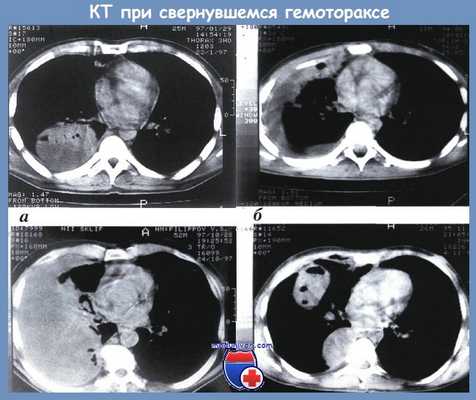

Формы свернувшегося гемоторакса по данным КТ:

а — локальный; б — плащевидный; в — тотальный; г — фрагментарный

На основании изучения результатов КТ с клинической точки зрения выделены 4 формы свернувшегося гемоторакса [Абакумов A.M.]: локальный, когда свертки крови расположены в синусах плевральной полости (чаще всего заднем), над диафрагмой, паракостально, паравертебрально, парамедиастинально и в междолевой борозде (рис. а); плащевидный, когда свертки крови располагаются одним блоком, узкой полосой, занимают синусы, паракостально и паравертебрально (рис. б); тотальный — свернувшийся гемоторакс объемом свыше 1500 см3 занимает одним блоком большую часть плевральной полости (рис. в); фрагментарный, когда имеются не связанные друг с другом, отграниченные скопления свертков крови в различных отделах плевральной полости и, как показывает опыт, в различных стадиях организации (рис. г).

Серийные срезы на уровне плевральных полостей позволяют установить локализацию осумкованных скоплений свернувшегося гемоторакса (верхушечная, базальная, междолевая, пристеночная, парамедиастинальная), их распространеность, конфигурацию и объем (в кубических сантиметрах) каждого из них, общий объем как жидкостной, так и плотной фракций, а также степень этой плотности, объективно выраженную в единицах по Хаунсфельду.

Кроме того, на компьютерной томограмме можно четко дифференцировать свернувшейся гемоторакс от внутрилегочных изменений. Совокупность информации, полученной при этом исследовании, дает возможность оценить особенности течения патологического процесса у каждого конкретного больного и определить адекватную лечебную тактику.